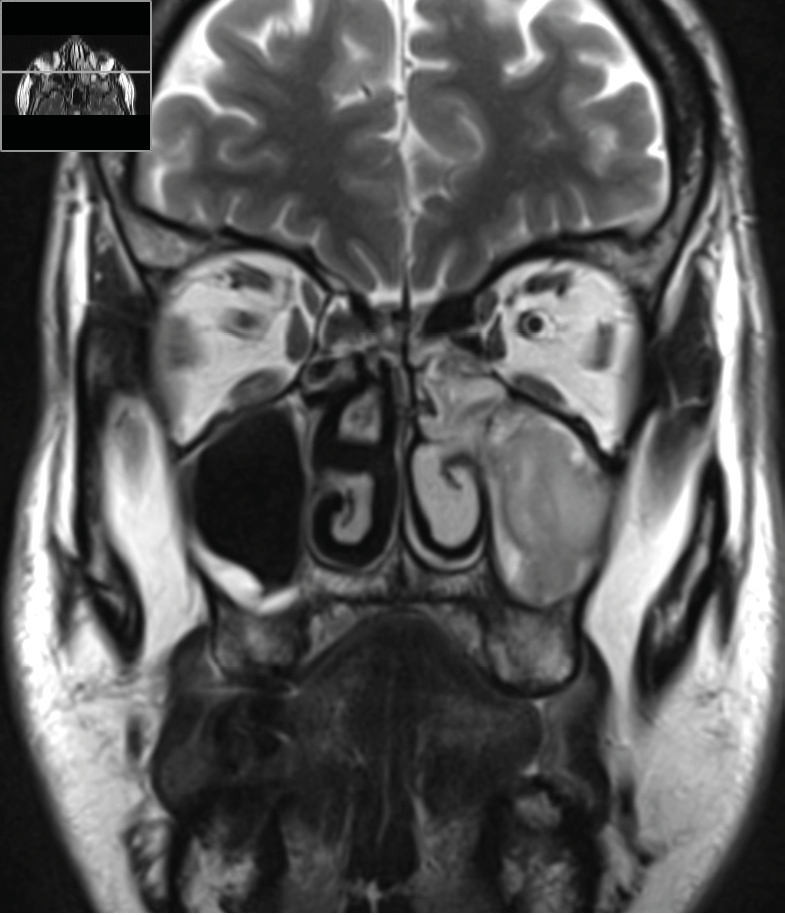

La tomodensitométrie des sinus retrouve un comblement complet unilatéral du sinus maxillaire gauche et des cellules ethmoïdales antérieures homolatérales, sans image de densité calcique intrasinusienne et sans lyse osseuse des parois (fig. 1). L’IRM montre un épaississement tissulaire de 23 mm de grand axe en regard du méat moyen gauche, avec un aspect de signal T2 hétérogène (fig. 2) et prenant le contraste en masse (fig. 3). Le comblement maxillaire gauche associé à un épaississement muqueux en cadre rehaussé correspond à une rétention en hypersignal en diffusion (fig. 4), avec diminution du coefficient apparent de diffusion (moyenne à 433 mm2/s) en faveur d’une pyocèle (fig. 5).